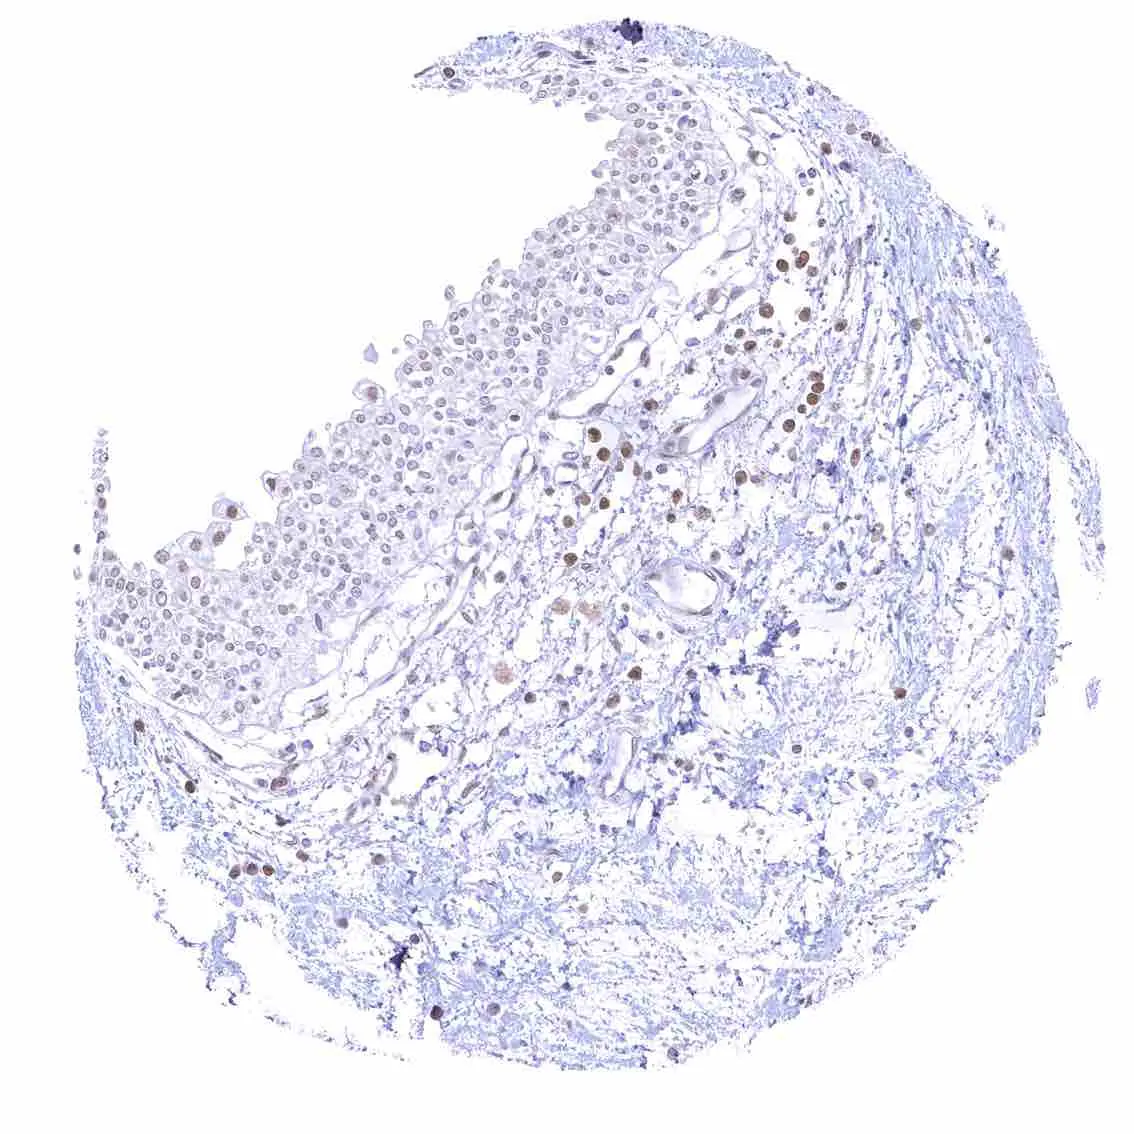

Esophagus, squamous epithelium – Nuclear staining of squamous epithelial cells predominates in the more mature cell layers (top 50_ of the epidermis).